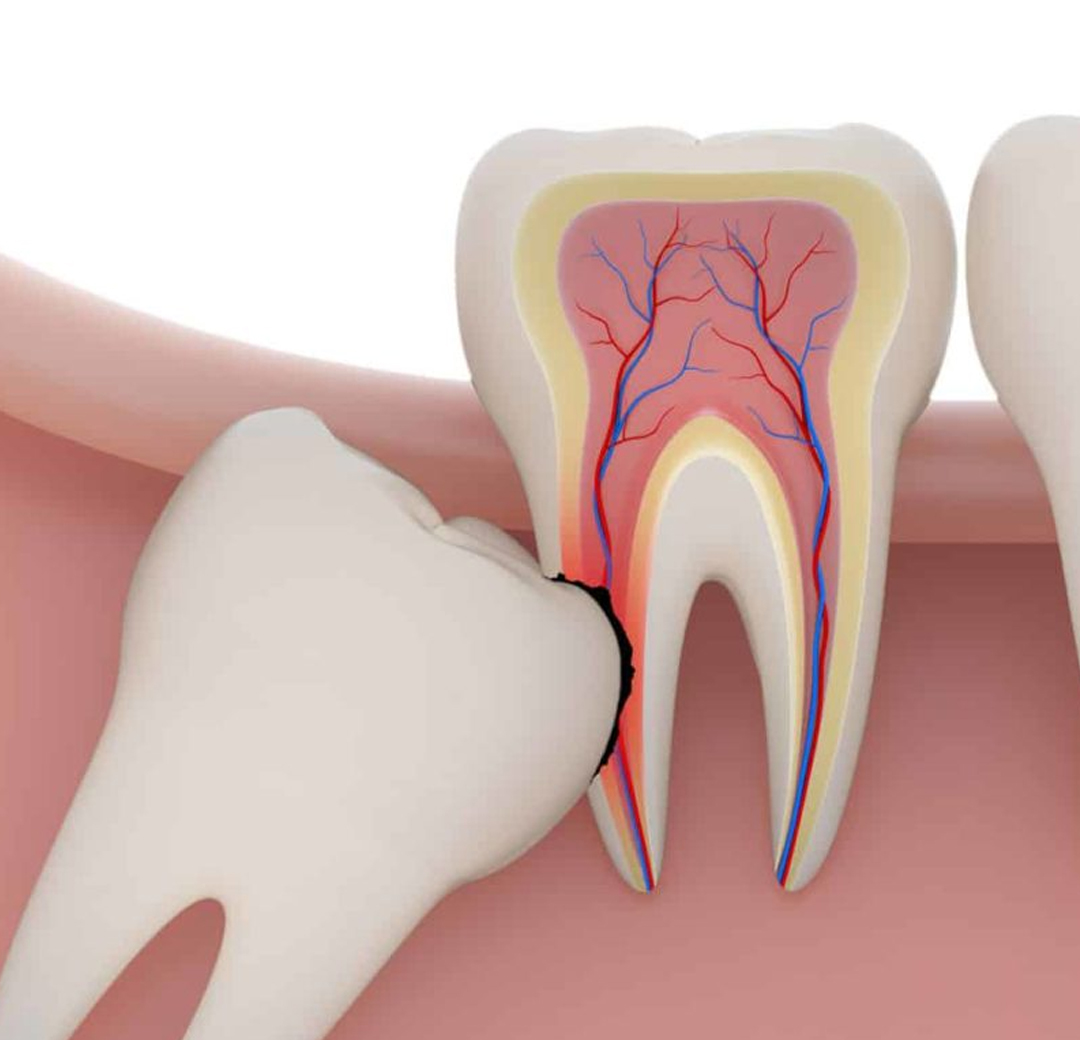

A extração do dente siso é indicada em algumas situações, dentre elas temos a falta de espaço na arcada, questões protéticas e/ou ortodônticas, presença de infecção em uma maior porção do dente ou do osso ao redor, lesões cariosas devido a incapacidade de uma higiene adequada, entre outros fatores.

Sim. Como são os últimos dentes a nascer, pode ser que os mesmos não encontrem espaço suficiente na boca. Dessa forma, essa falta de espaço pode acarretar uma movimentação dos outros dentes, provocando assim um desalinhamento, que além de atrapalhar a estética, dificulta a higienização.

Correto. Muitas pessoas relatam desconforto quando os dentes sisos estão nascendo. Isso se deve, principalmente, ao acúmulo de bactérias no local, que pode acarretar em um processo inflamatório e até mesmo infeccioso. Além da dor, um inchaço na região pode estar presente e em situações mais severas o paciente desenvolve uma dificuldade de abertura bucal. É extremamente necessário realizar uma consulta com o dentista nessas situações, pois existe o risco dessas bactérias caírem na corrente sanguínea, comprometendo não somente o local em questão, mas o organismo como um todo. Por isso, em alguns casos, é necessário a extração do dente siso.